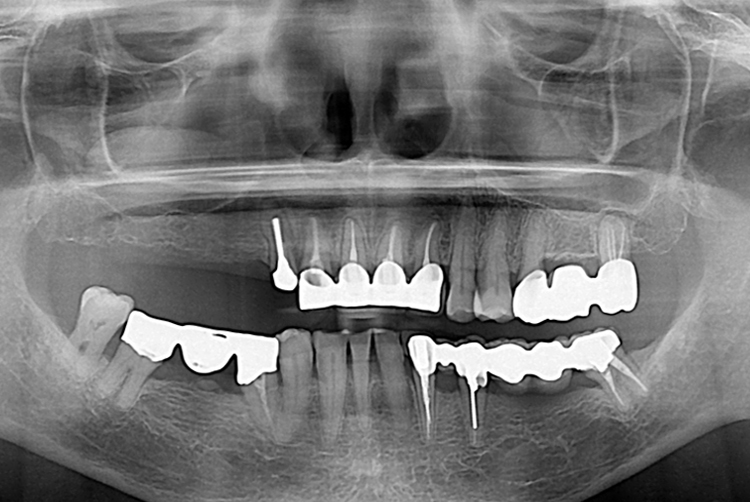

치료전 : 2017-01-11

세종치과는 많은 환자와 다양한 케이스를 바탕으로 항상 편안한 임플란트 수술을 제공하고자 노력하고,

오래동안 튼튼히 쓸 수 있는 임플란트 수술을 가장 큰 목표로 삼고 있습니다